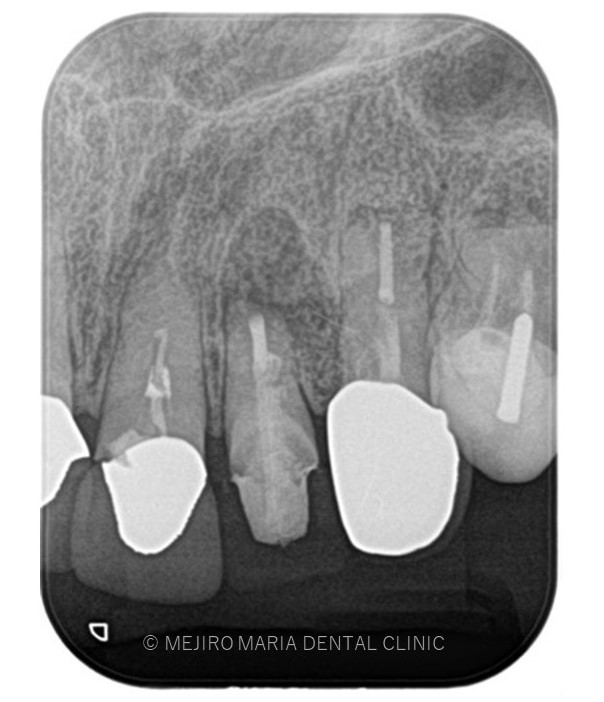

でのリカバリー_該当歯牙の精密根管治療後のレントゲン画像.jpg)

治療詳細